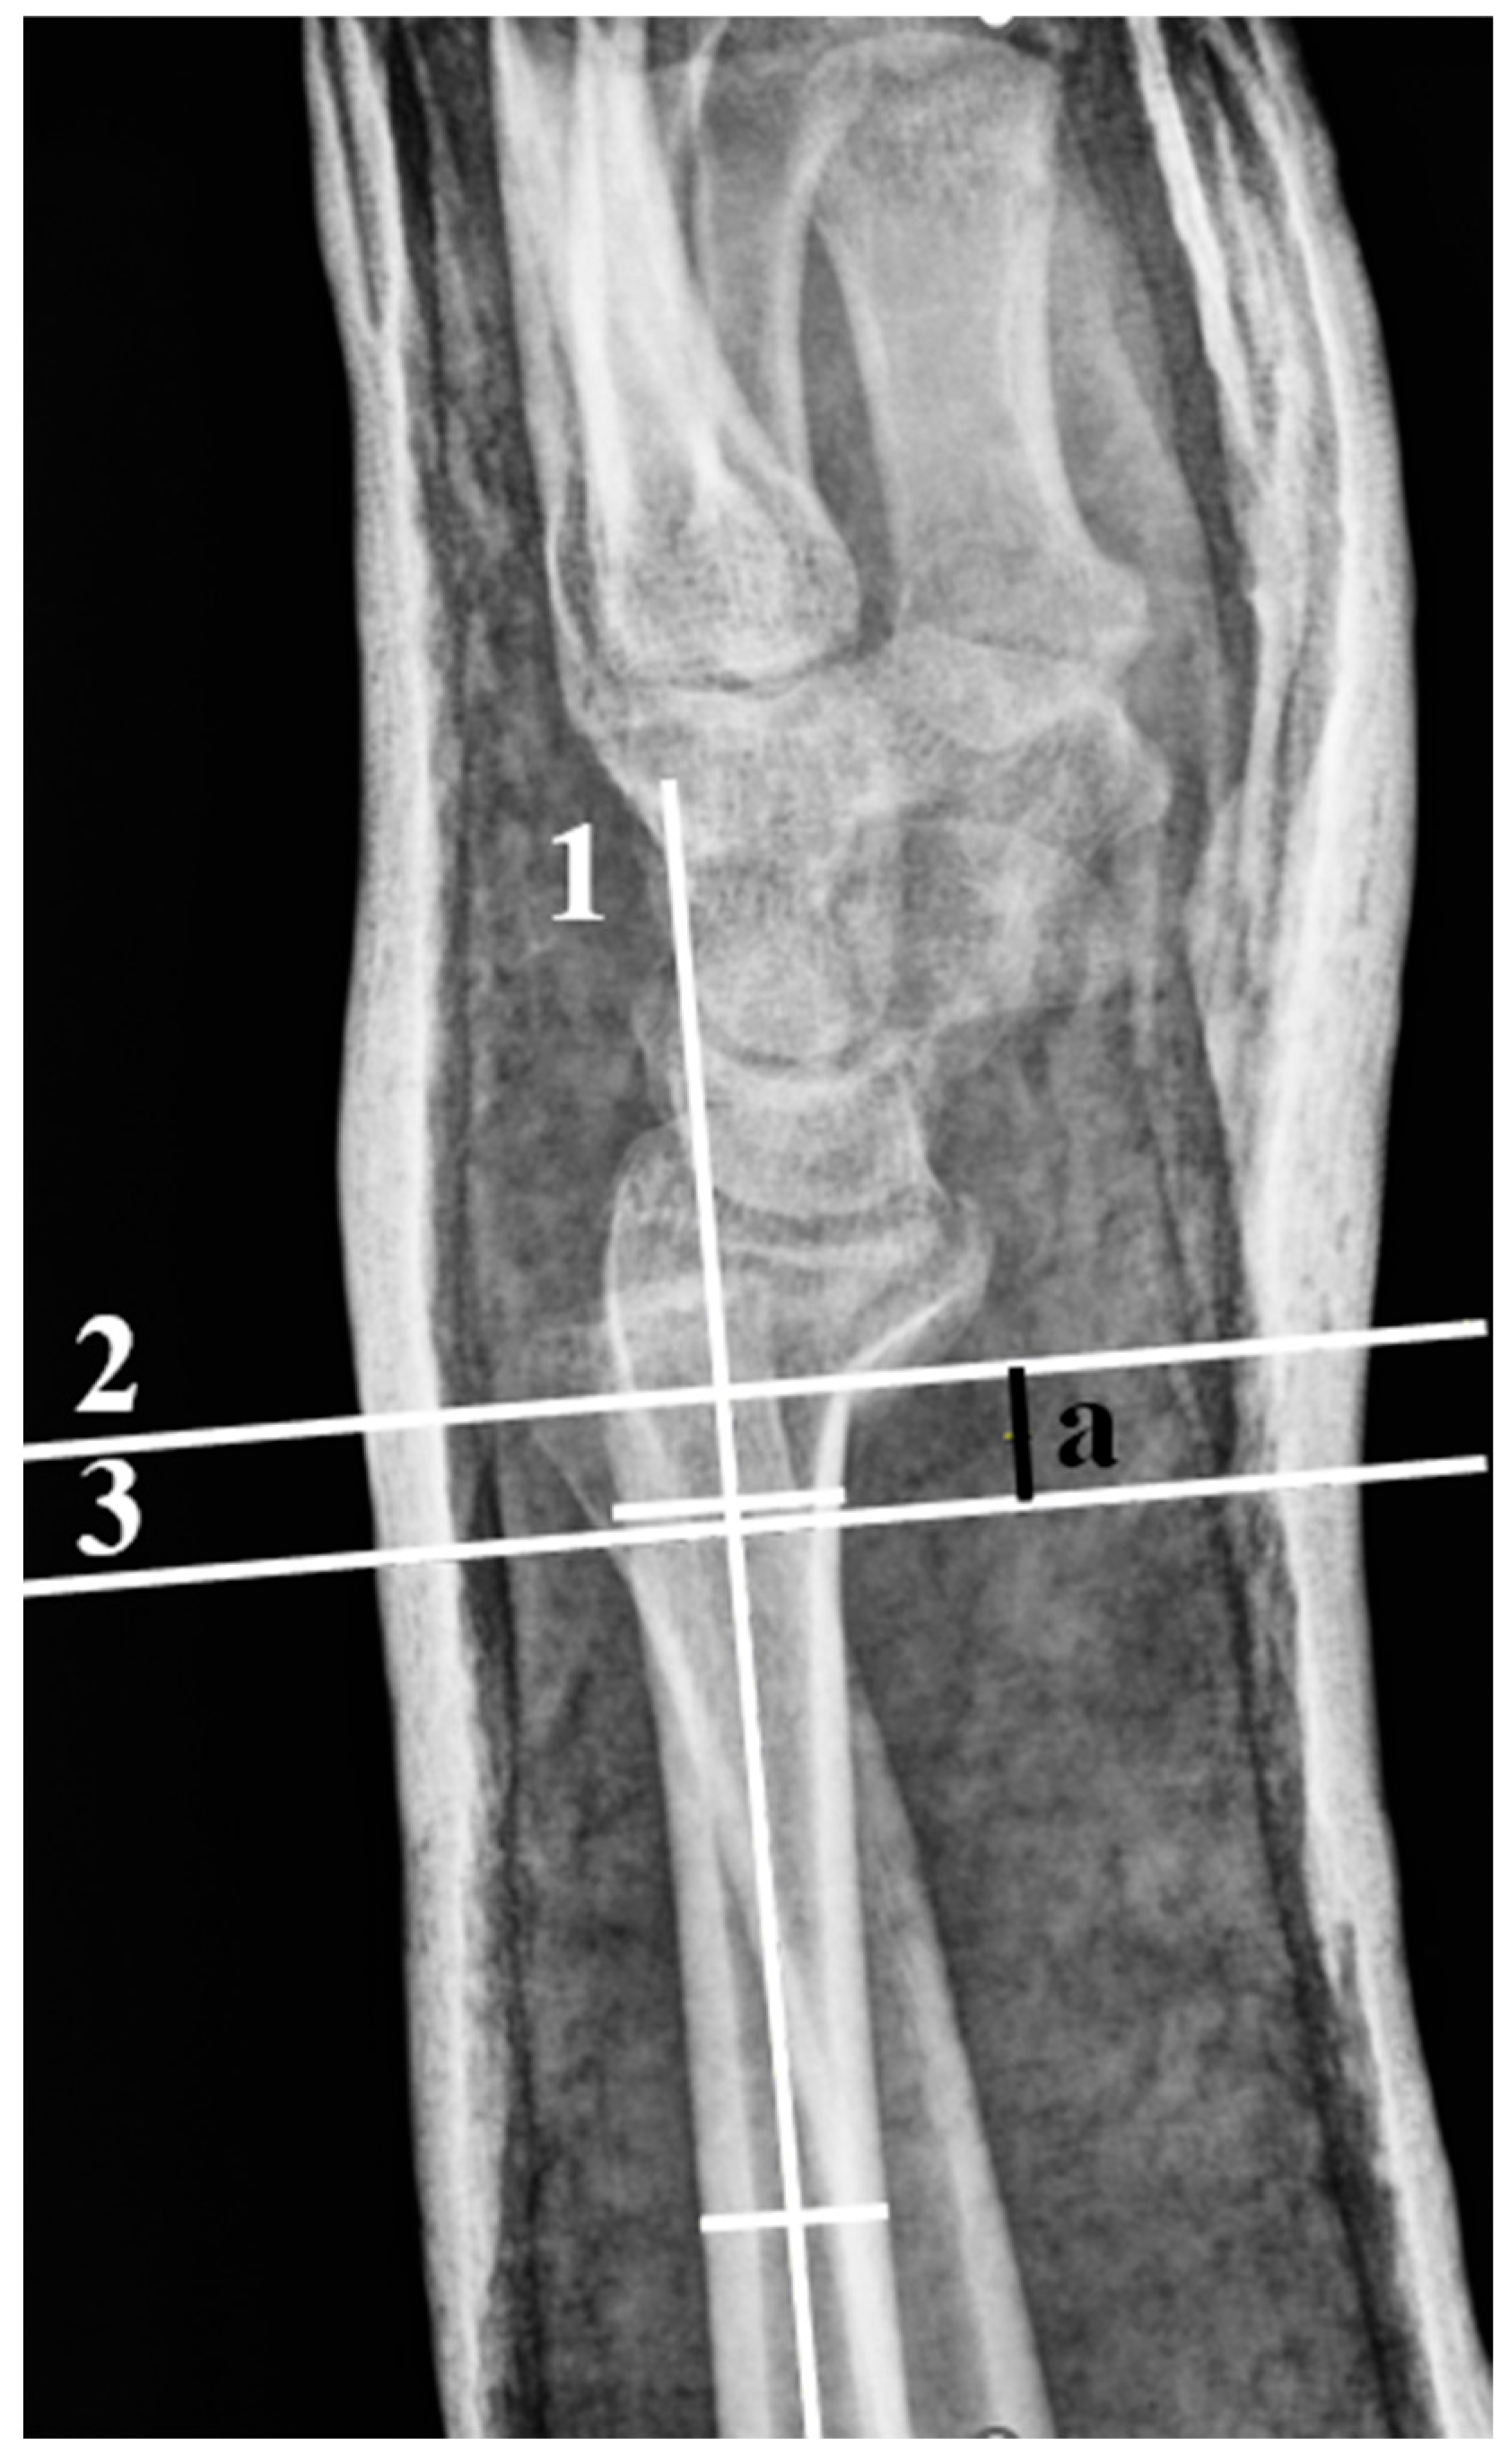

| DA | Dorsal Angulation |

| RI | Radial Inclination |

| RH | Radial Height |

| RS | Radial Shortening |

| RT | Radial Translation |

| UV | Ulnar Variance |